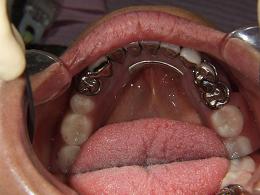

コンフォート義歯

内面に軟らかい生体シリコーンを貼りつけています

お口の中に入れた状態です!